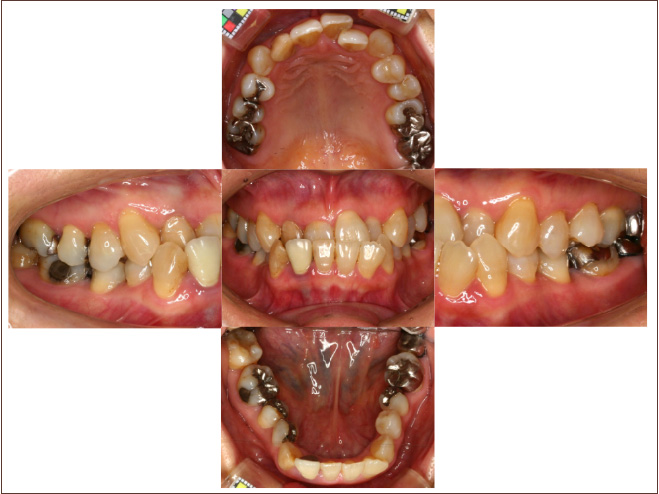

狭い歯列(狭窄歯列)によって、舌が歯列の中に収まらない状態です。

●高口蓋 ●低位舌 ●口呼吸

狭窄歯列(高口蓋)

狭窄歯列(低口蓋)

狭窄歯列(低位舌)

右のように、狭窄歯列だと舌は、狭い歯列に阻まれて、前方や上方の口蓋に自由に動くことができません。その結果、舌は低い位置(低位舌)にあり、前方に出ず後方に位置するので、気道が狭くなってしまっています。

一方、左のように、広い歯列だと舌は、前方にも上方にも自由に動けるので、舌は普段は口蓋についていて鼻呼吸が無理なくできているのです。

狭い歯列(狭窄歯列(きょうさくしれつ))

高口蓋(上顎が深い→鼻腔が狭い)

舌が歯列に納まらない→低位舌

歯並びが悪い

かみ合わせが悪い